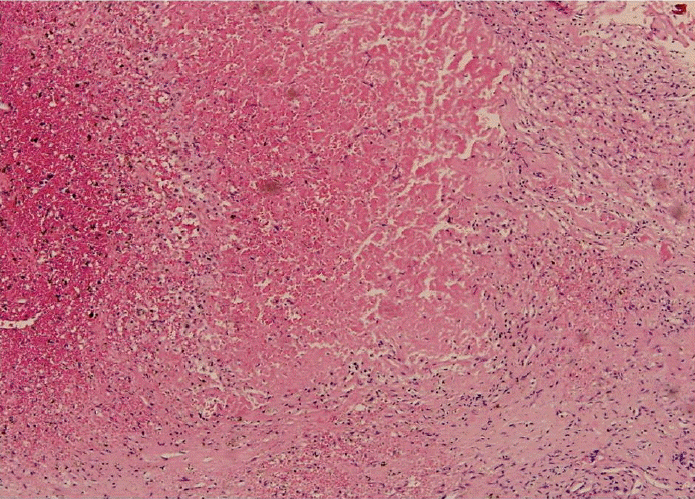

Figure 3.

Microscopically, there is extensive necrosis with focal pituitary gland cells in the right lower area (H&E, ×100).